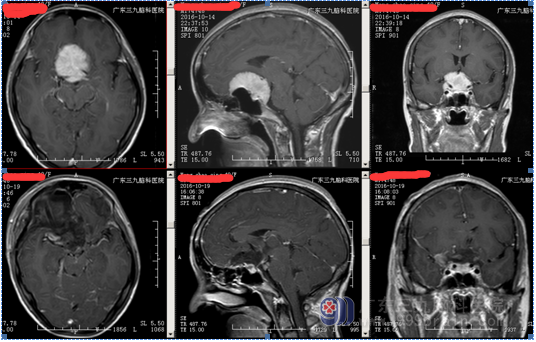

行全麻下右侧扩大翼点入路鞍结节脑膜瘤切除术。术中见右侧视神经、颈内动脉被肿瘤包绕,肿瘤血供丰富,肿瘤起源于鞍结节及鞍隔。术中全切肿瘤,神经、血管、垂体柄完好。术后病理示:鞍区脑膜瘤,部分为过渡细胞型,部分为血管瘤型脑膜瘤,WHO I级。术后左侧视力同术前,右侧视力较术前稍差。 经系统的治疗后康复出院。

广东三九脑科医院神经外一科张良主任介绍:鞍结节脑膜瘤的手术入路应根据肿瘤的大小及其生长部位等进行选择。常见的手术入路包括单侧额底入路、双侧额下入路、翼点入路、双额纵裂入路等,每种手术路径各有其优缺点。国外专家认为,肿瘤直径较小时采用单侧额底入路效果较好,但易损伤嗅神经及额叶;对于巨大型肿瘤易采用双额纵裂入路;对于居中线一侧向鞍后生长的肿瘤易采用翼点人路,因其不易由于牵拉而损伤嗅神经及额叶。但无论选择何种手术路径,都应先充分释放脑脊液,以降低颅内压和分开或抬起额叶,从而扩大手术视野。本例患者肿瘤起源于鞍结节,肿瘤从前颅窝底一直生长到上斜坡,所以选择翼点入路,手术中主要从第一间隙操作,全切肿瘤,垂体柄保留良好,没有尿崩。手术入路选择除了考虑肿瘤的情况外,还要考虑手术者对入路的熟悉情况。

血管瘤型血供丰富,控制术中出血尤其重要。术前通过影像学了解肿瘤的供血情况,术中优先对肿瘤基底部(鞍结节处)进行处理,阻断其血供,从而减少术中出血,鞍隔处不要急于处理,以免损伤垂体柄。之后再对肿瘤进行分块切除,应先从无重要结构的中心部位进行分块切除。剥离小块肿瘤时应谨慎,避免拉断其周围的神经、血管等,还应尽量减少对视神经的牵拉,切勿损伤视器的血供,同时手术应保持在蛛网膜下腔内操作,尽量避免直接损伤视神经。